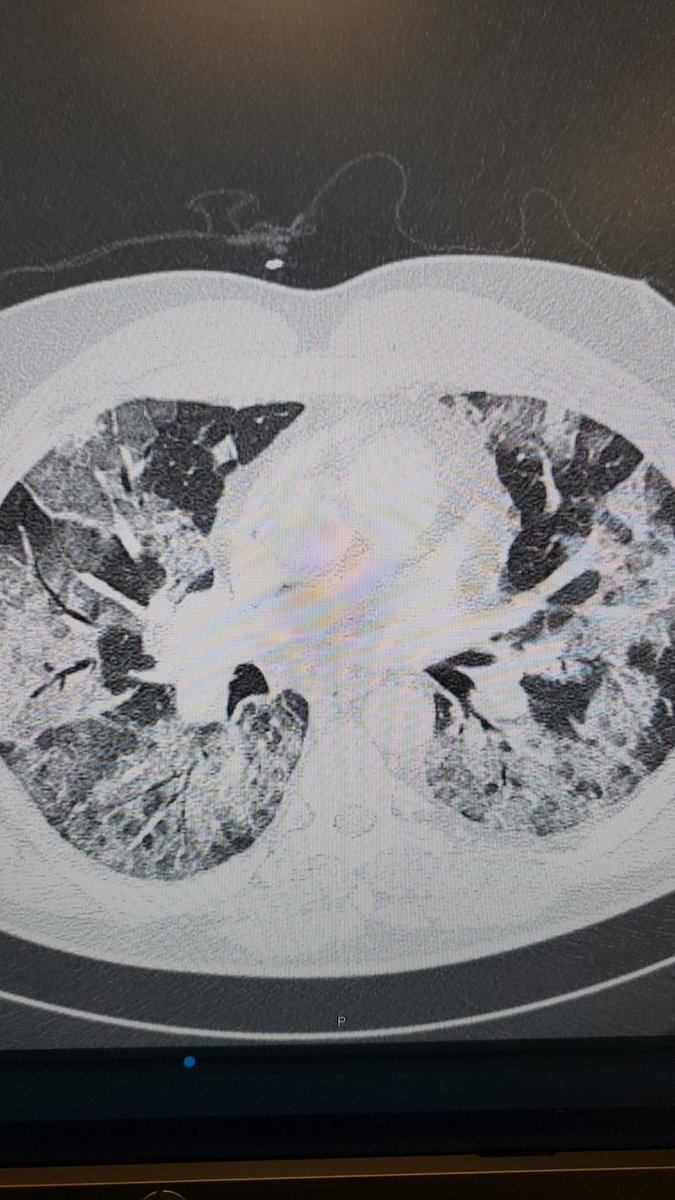

I've resorted to showing healthy people their COVID-mutilated lungs on CT in an effort to get them to tell their friends and family to be vaccinated. Young. (Previously) healthy.

I've resorted to showing healthy people their COVID-mutilated lungs on CT in an effort to get them to tell their friends and family to be vaccinated.

Young. (Previously) healthy.